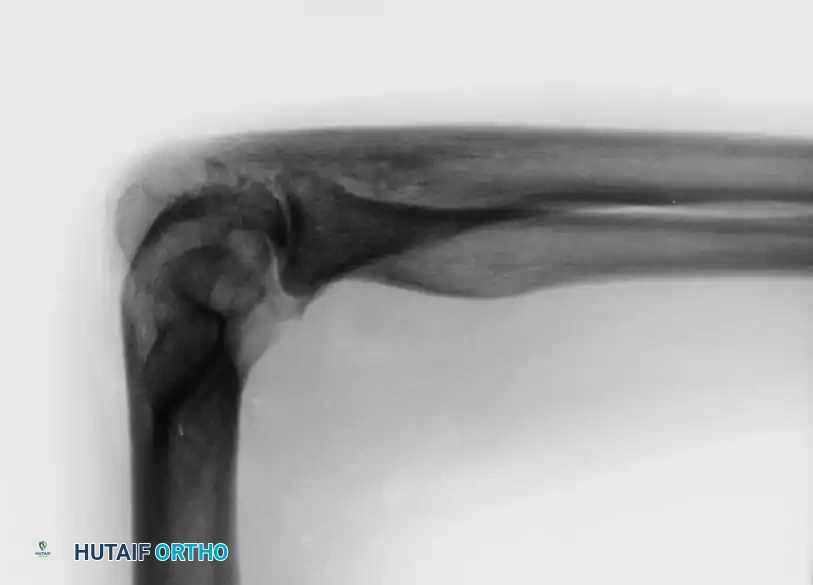

Associated Surgical & Radiographic Imaging